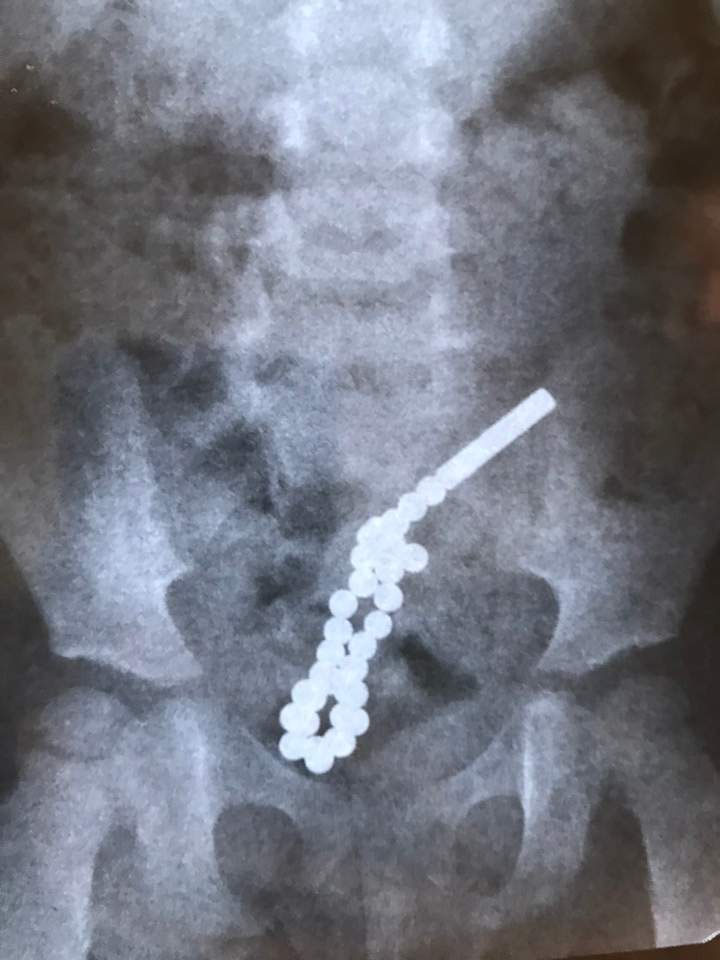

Во Львове хирургам львовской городской детской больницы пришлось экстренно оперировать двухлетнюю девочку, проглотившую 30 сильно намагниченных шариков. Хирургическая операция по спасению ребенка продолжалась почти два часа, сообщает ZAXID.NET.

По словам детского хирурга Дмитрия Грицака, девочка поступила в больницу с жалобами на боль в животе. Рентген показал, что достать шарики было бы нереально, поэтому приходилось делать операцию традиционным способом — через разрез на животе.

«Эти неодимовые магнитики очень мощные. Ребенок проглотил 31 такой магнитный шарик. Часть из них попала в одну петлю кишечника, другая — в другую. В кишечнике они между собой соединились и пробили семь дыр в стенках кишечника», — рассказал Грицак.